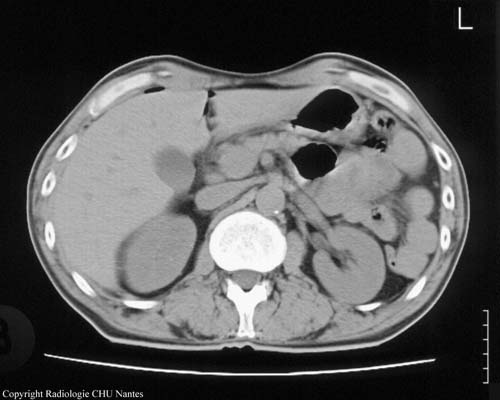

PNEUMOPÉRITOINE 2

Sommaire PNEUMOPÉRITOINE...